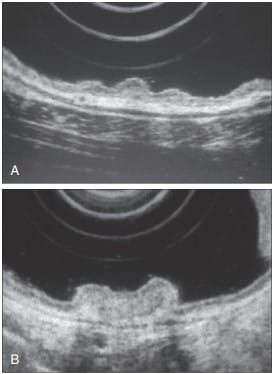

Early-Stage Cancer and Nodal Involvement

For early-stage esophageal and gastric cancers, EUS’s role primarily revolves around ruling out nodal involvement, a key factor in determining the disease’s progression.

EUS-guided FNA is instrumental in staging T1 or T2 esophageal and gastric cancers. Accurate determination of nodal involvement is critical in deciding between neoadjuvant chemoradiotherapy and direct surgical approaches.